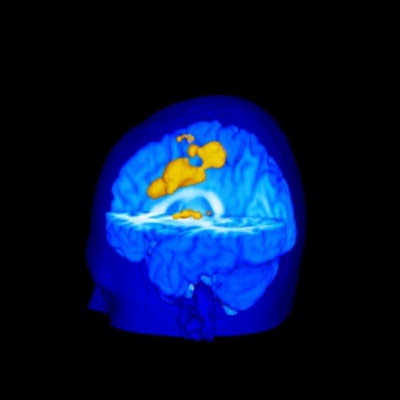

The subjects reporting greater pain from the heat stimulus also showed on MRI an increased activation of the primary somatosensory cortex (pain location and sensitivity center) and the anterior cingulate cortex (area processing the unpleasant feelings evoked by pain).

Pain-induced brain activation in highly sensitive individuals as assessed with fMRI. Note that the primary somatosensory cortex and anterior cingulate cortex had a greater magnitude of activation in sensitive individuals (above). In insensitive individuals, the thalamus displayed generally similar activation (below). Images courtesy of Robert Coghill, Ph.D.

The investigators also found insignificant MRI variations between subjects for activation of the thalamus, which participates in pain signal transmission from the spinal cord to higher brain regions.

"This difference between cortical and thalamic patterns of activation may help explain pain differences between individuals," said Coghill. "This finding raises the intriguing possibility that incoming painful information is processed by the spinal cord in a generally similar manner. But, once the brain gets involved, the experience becomes very different from one individual to the next."